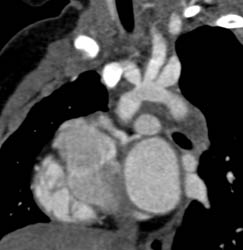

Patent Bypass Graft in Multiple Views With Multiple Renderings